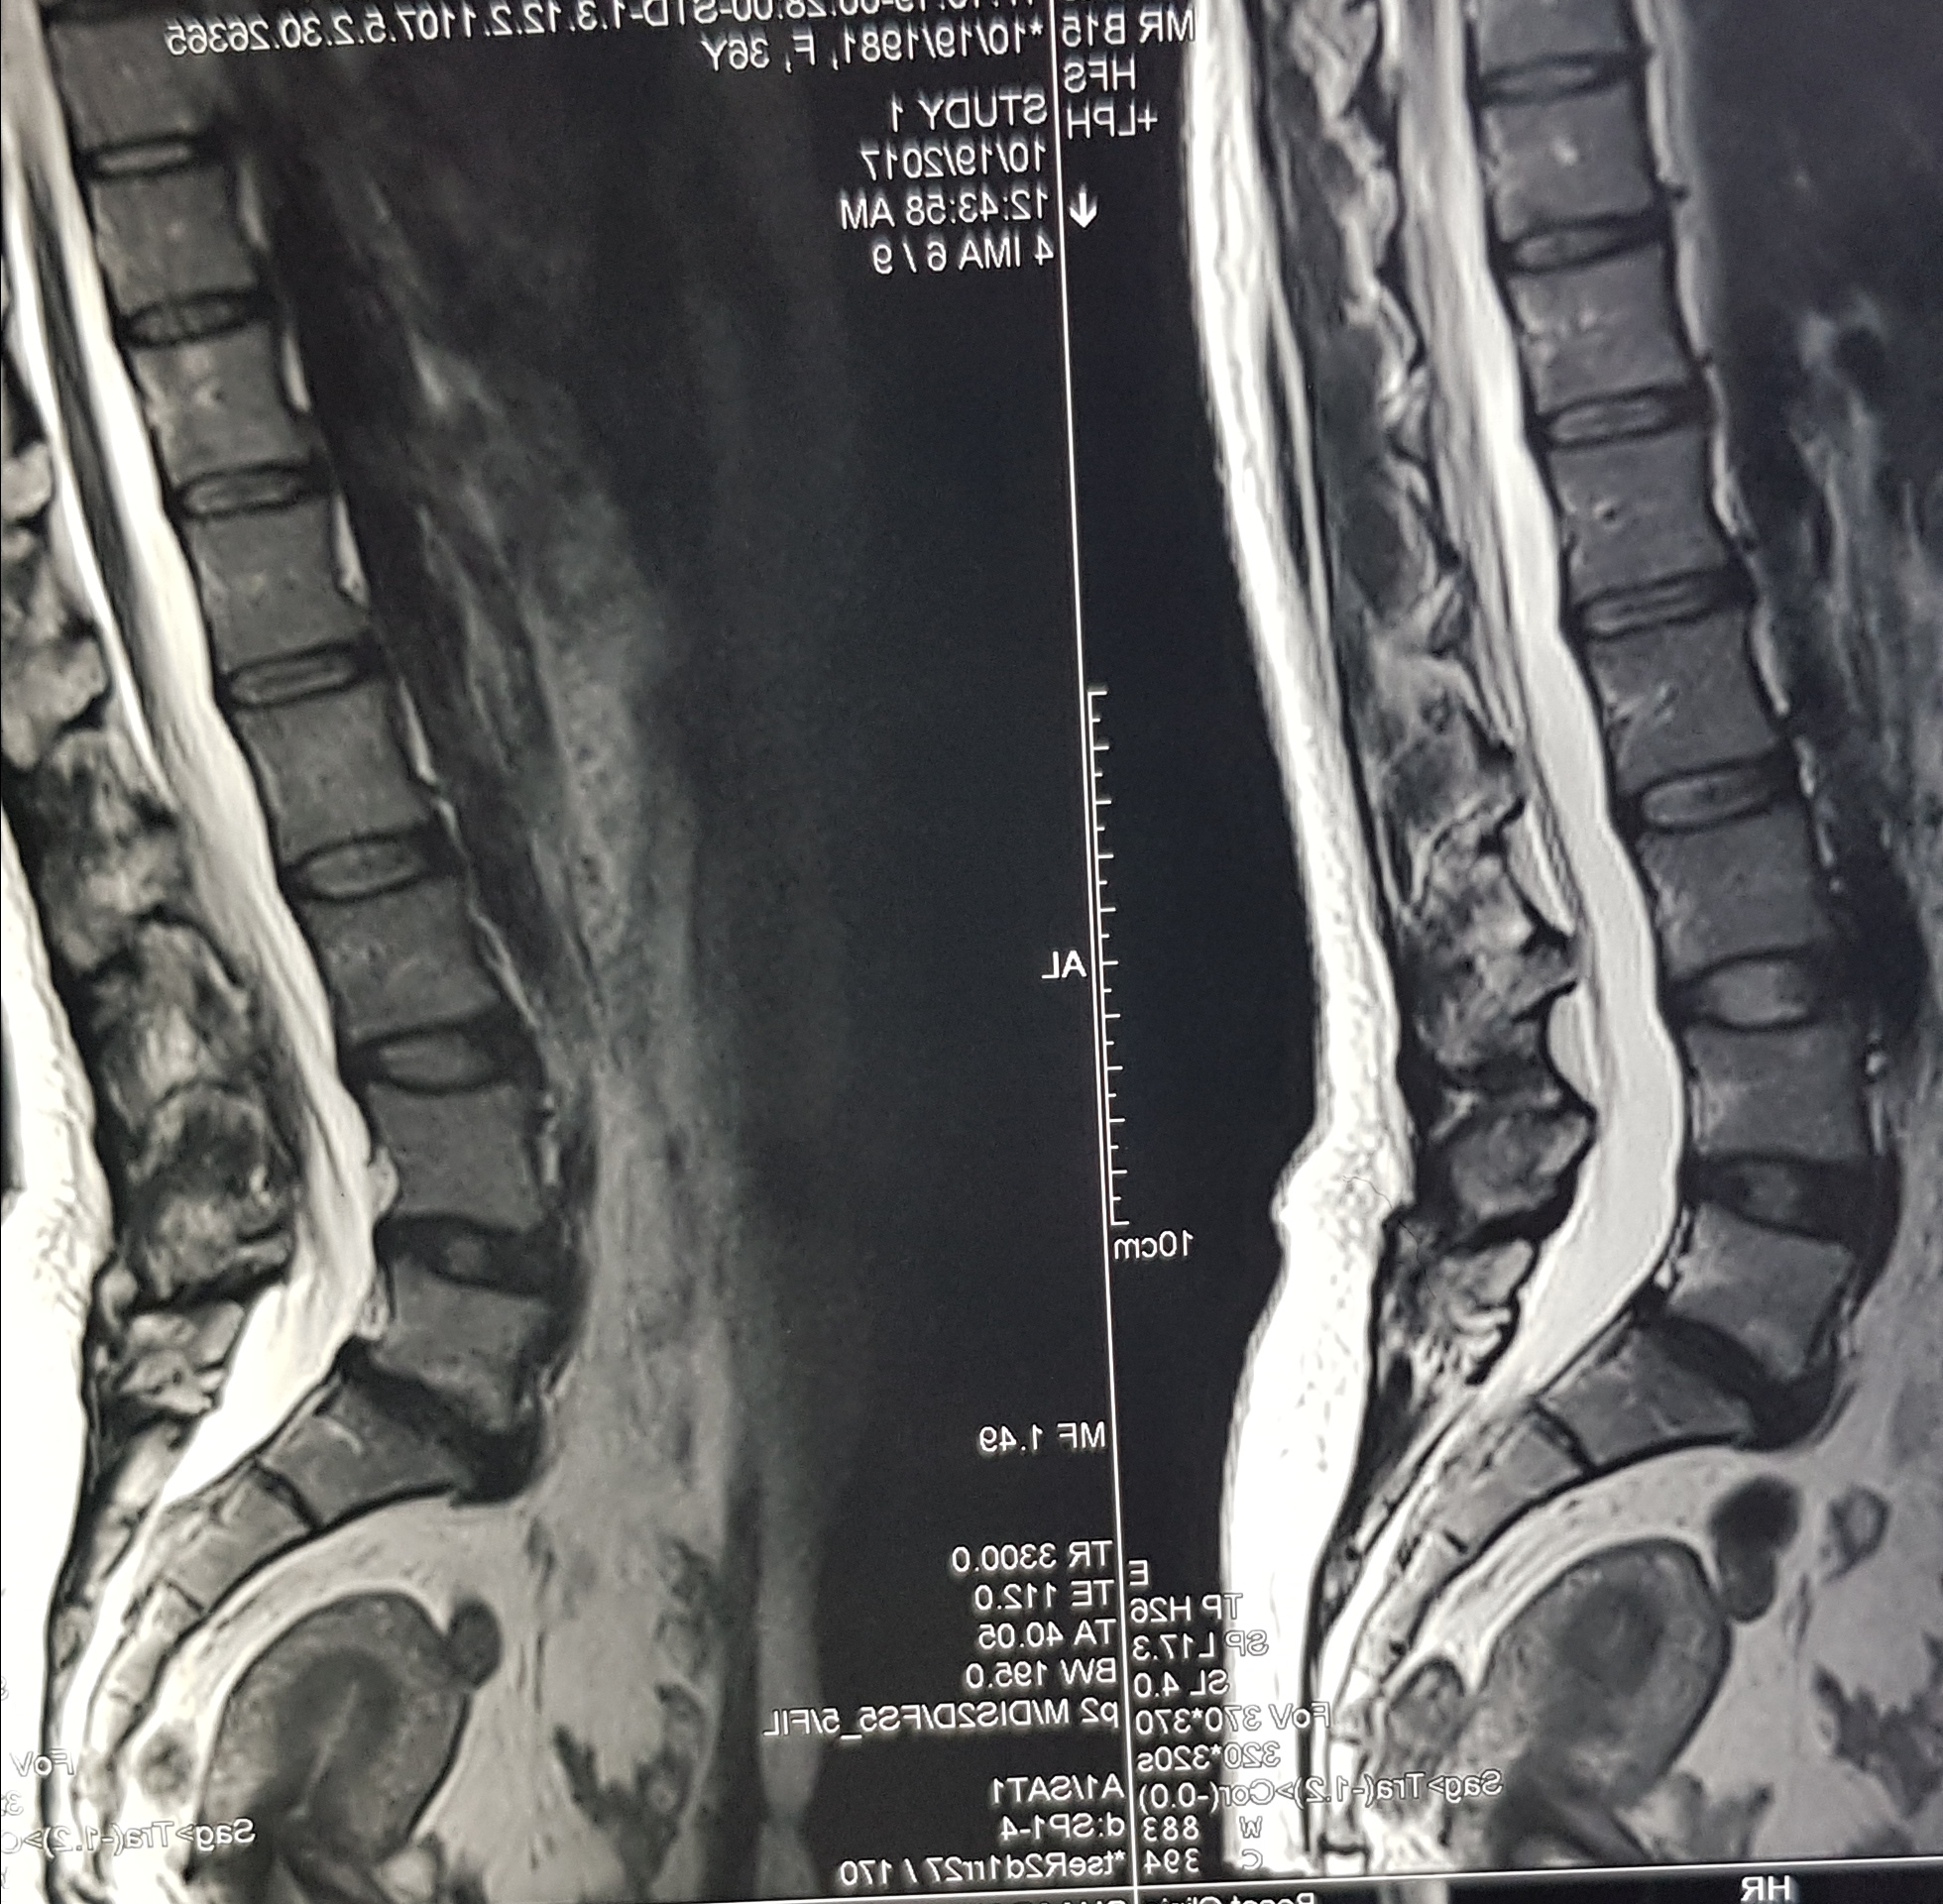

به اینجا که رسید مدارکش را یکی یکی از پاکت بیرون آورد و ادامه داد :جراح به من پیشنهاد عمل جراحی داد و گفت در صورتی که درنگ کنم ممکن است که حرکت پاهایم را از دست بدهم یا تا آخر عمرتوانایی کنترل ادرارم مختل شود . شب به منزل رفتم و تا صبح از کابوس فلج شدن بیدار ماندم .نهایتا پس از چند روز استرس تن به تیغ جراح دادم و عمل جراحی کردم و به امید بهبودی صبر کردم . صبر کردم و درد کشیدم به امید اینکه بهتر شوم ولی…بغض گلویش را گرفته بود . بیمار با درد سوزش و احساس ضعف در پایش مراجعه کرده بود .دردی که امانش را بریده بود و در این شش ماه از انجام هیچ کاری برای درمان فروگذار نکرده بود. درحالیکه با حرف زدن سعی در آرام کردنش داشتم یکی یکی مدارکش را بررسی کردم .یک ام ار ای جدید بود مربوط به بعد از عمل که آثار گذاشتن شش عدد پیچ و دو تا پلاتین در آن مشخص بود (عکس سمت چپ بالا) در محل عمل چسبندگی دیده میشد و من شروع کردم به معاینه بیمار و توضیح درباره اینکه من میتوانم با تزریق آنزیمی در اتاق عمل چسبندگیها را تا حد زیادی باز کنم و تلاش کنم تا دردهایش کمتر شود. بیمار چند کلیشه ام ار ای را از پاکت بیرون آورد و با نگرانی گفت : میشه این مدارک من رو که مربوط به قبل از عمله نگاه کنید؟

ام ار ای رو دیدم عکسهای دینامیک رو یکی یکی نگاه کردم …نفسم حبس شده بود .نمیخواستم به بیمار استرس وارد کنم . دیسک خفیف در ام ار ای که تو عکسهاش علایم بی ثباتی نداشت .چرا عمل شده؟؟ نه علایم شدیدی نه دیسک بزرگی نه جابجایی مهره .آخه چرا با چه تشخیصی و با چه مجوزی ؟